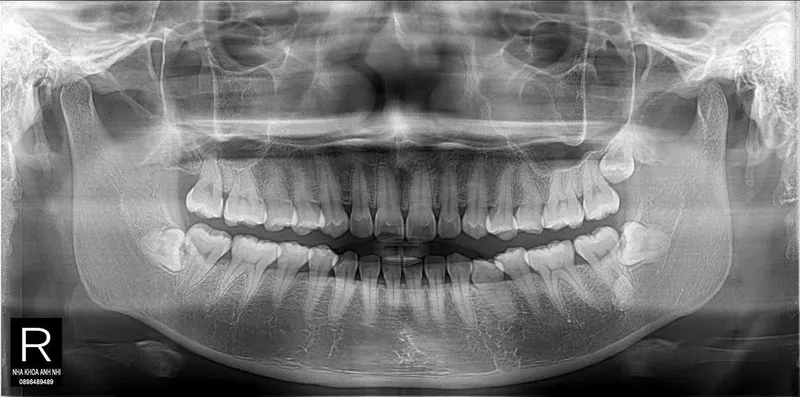

Chính vì là kẻ đến sau cùng, răng khôn thường không tìm được vị trí thuận lợi để mọc thẳng. Chúng phải tìm cách chen chúc, dẫn đến các tình trạng phổ biến như mọc lệch, mọc ngầm dưới nướu hoặc đâm ngang vào chiếc răng số 7 bên cạnh.

Hủy hoại cấu trúc răng số 7 lân cận

Khi răng khôn mọc lệch hoặc đâm ngang, nó sẽ trực tiếp húc vào chân răng số 7. Lực đẩy này diễn ra âm thầm nhưng mạnh mẽ, làm tiêu chân răng, gây sâu răng số 7 và có thể khiến chiếc răng này bị lung lay hoặc mất vĩnh viễn.

Nguy cơ hình thành u nang xương hàm

Trong một số trường hợp răng khôn mọc ngầm hoàn toàn trong xương, các mô bao quanh răng có thể phát triển thành u nang.

Nếu không được phát hiện qua phim chụp X-quang, u nang này sẽ âm thầm phá hủy xương hàm, làm tổn thương các dây thần kinh và các răng xung quanh, gây ra những tổn thương nặng nề khó phục hồi.